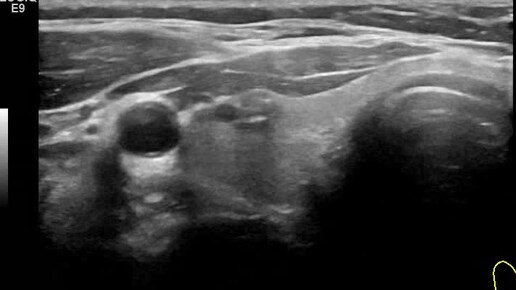

Видео к статье "Стратификация узлов щитовидной железы. TI-RADS-4" https://dzen.ru/a/ZwNx-uQp-Sfk6L46

Ультразвуковые находки от врача УЗД Зорина Я.П.